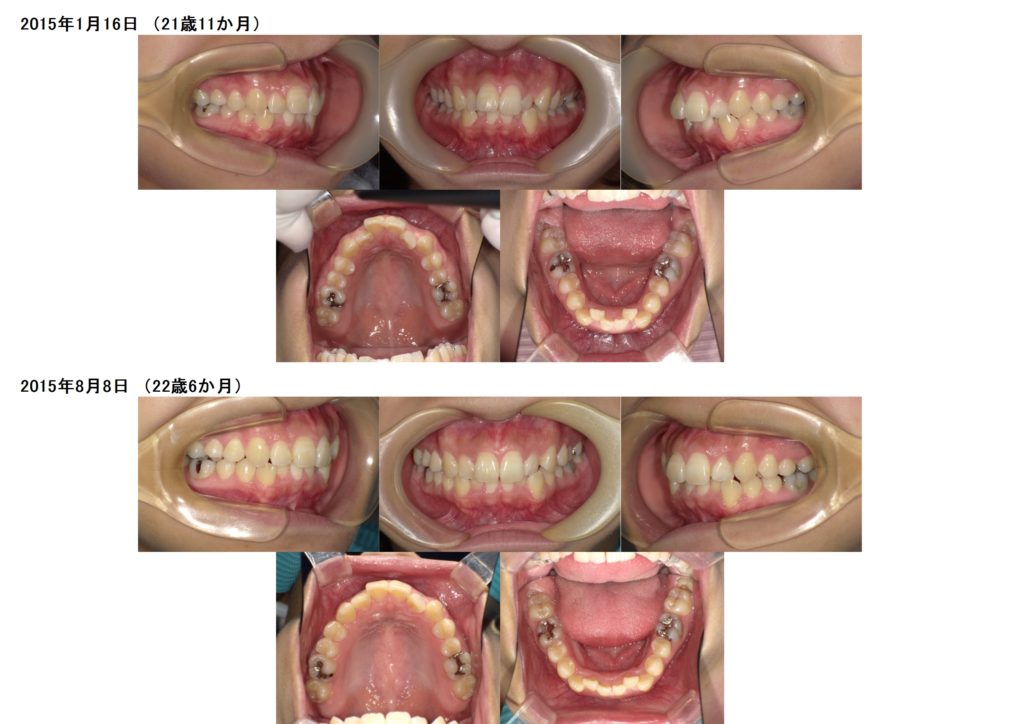

抜歯の治療例の写真

↑上下4番目の歯を左右抜歯し、約半年間側面にブラケットを装着しました。

↑抜歯、突出ケースでもしっかりとマウスピースを使うとこんなに早く変化が分かります。ここから再度噛み合わせの微調整に入るためのマウスピースを作成します。